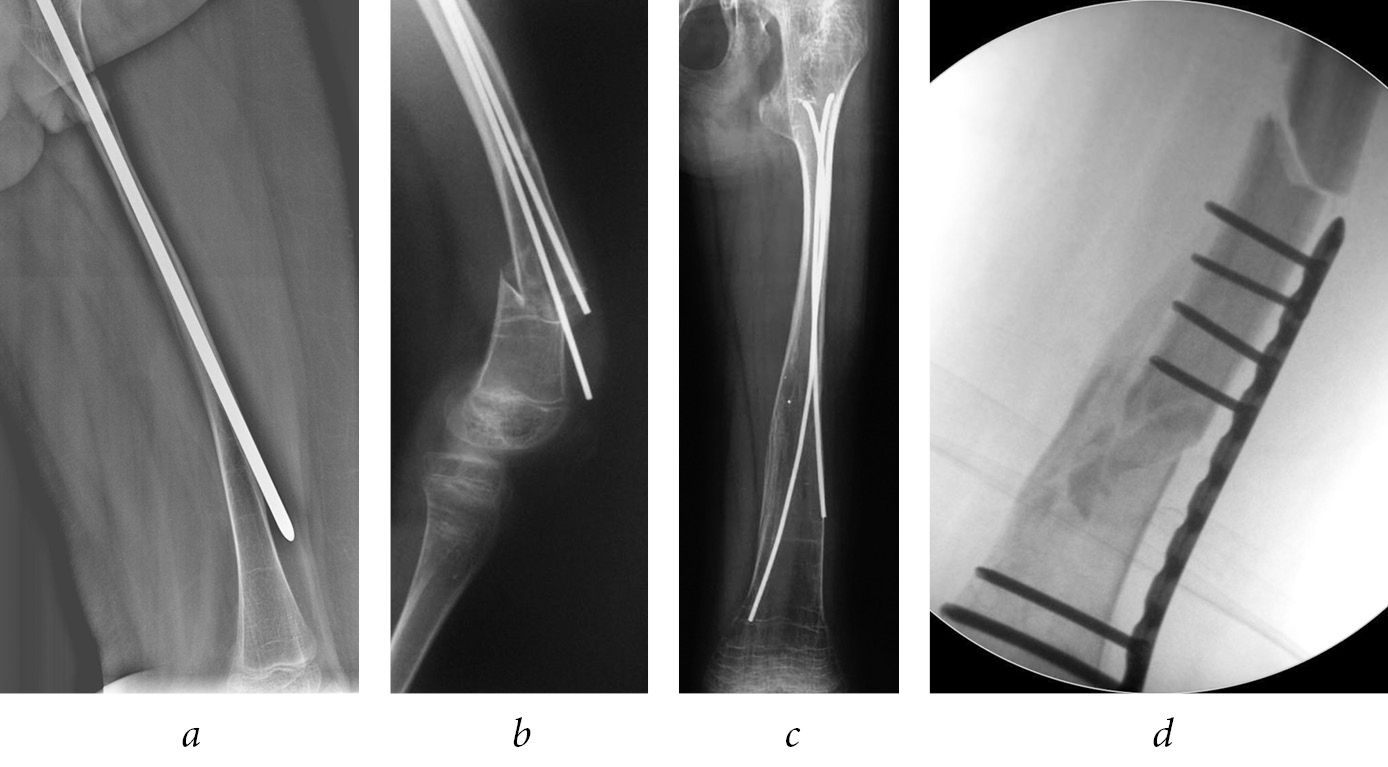

Intramedullary osteosynthesis with a telescopic rod is associated with the risk of rod deformation (Fig. 5, a), disconnection of the ends of the rod (Fig. 5, b), violations of the telescopic effect (Fig. 5, c), migration of the rod into the soft tissue and joint cavity (Fig. 5, d), eruption of the distal end of the rod through the anterior cortical layer of the metaepiphysis, metal fixator fracture, and rotational instability.

Fig. 5. Intramedullary fixation with a Sheffield rod, deformation of the solid part of the rod (a) [51]; telescopic rod disconnection (b); migration of the distal end of the telescopic rod (c); migration of T-shaped tip Bailey–Dubow pin (d) [56]

Non-telescopic fixators also migrate often (Fig. 6, a). Their use raises the risk of reimplant fractures (Fig. 6, b), and revision operations to replace them with a longer fixator are required more often (Fig. 6, c). On average, the frequency of revision operations after using non-telescopic fixators is 3.5 times higher than that after using telescopic fixators [54]. A review of the literature has shown that the average durability of non-telescopic structures is 2–2.5 years [50, 53–57].

The isolated use of plates is considered inexpedient because of the high risks of reimplant fractures associated with the stress load on the bone at the edge of the plate (Fig. 6, d) [60]. However, the literature describes a combined approach, wherein an intramedullary fixator and a plate were used. Thus, Cho et al. suggested using plates with a monocortical screw insertion to ensure rotational stability and subsequently removing the plate after consolidation [61]. In some cases, Popkov et al. applied counter transphysary osteosynthesis with two TENs, combining it with transosseous osteosynthesis with the Ilizarov apparatus, to achieve rotational stability [62].

Fig. 6. The eruption of the rod through the anterior cortical bone layer (a); reimplant fracture (b); bone growth outside the splint area (c); reimplant fracture after osteosynthesis with plate (d)